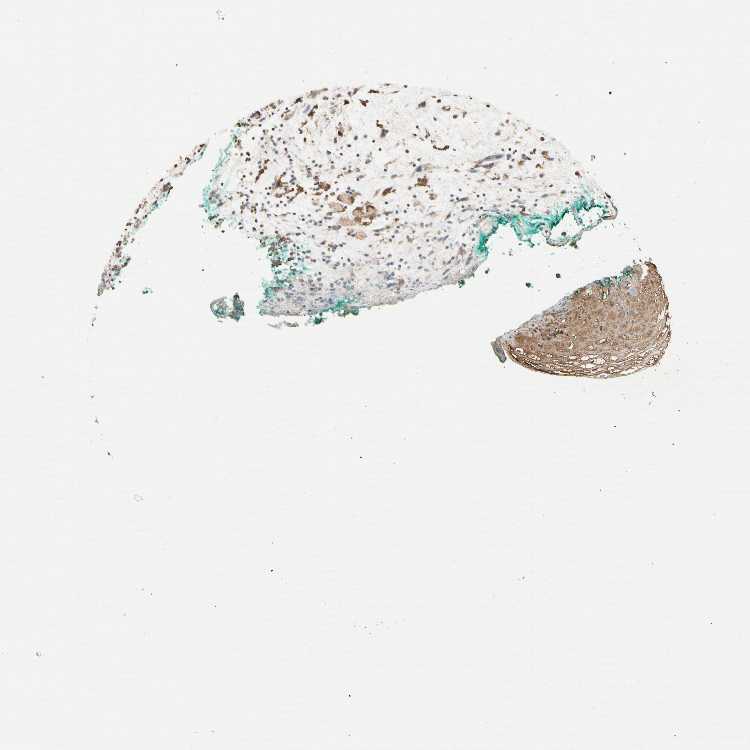

TISSUE PRIMARY DATA ORAL MUCOSA Show tissue menu

ORAL MUCOSA - Antibody stainingi

Antibody staining in the annotated cell types in the current human tissue is reported as not detected, low, medium, or high, based on conventional immunohistochemistry profiling in selected tissues. This score is based on the combination of the staining intensity and fraction of stained cells.

Each image is clickable and will lead to virtual microscopy that enables deeper exploration of all samples and also displays staining intensity scores, fraction scores and subcellular localization as well as patient and tissue information for each sample.

Antibody HPA007047Antibody HPA007456Antibody CAB025274

Squamous epithelial cells LowMediumNot detected